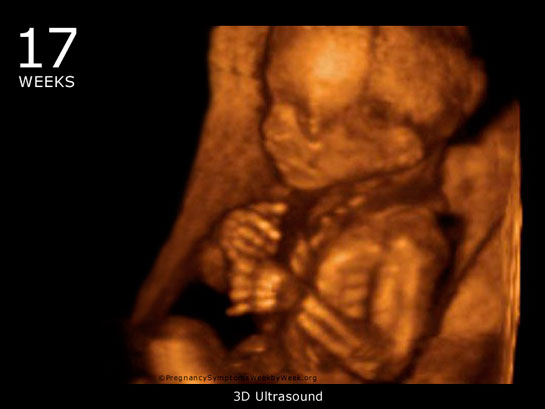

36 haftalık gebelik sürecinde yaşadıklarım gerçekten çok ilginç. Bebeğimin boyunun 47 cm ve ağırlığının 2 kg 700 gram olması beni heyecanlandırıyor. Her gün ortalama 30 gram alması da bu süreçteki gelişimini gösteriyor. Bebeğin doğuma hazırlandığını bilmek güzel ama bu haftayı atlatmanın verdiği rahatlıkla birlikte üzerimdeki yükün biraz hafiflemesi de sevindirici. Hormonal değişimler nedeniyle bedenimdeki gevşeme ve yumuşama beni yavaşlatıyor. Yürüyüşlerim değişti, bu da normal. Ancak bel ve pelvisteki ağrılar beni rahatsız ediyor. Yemek yeme konusunda da sıkıntılar yaşıyorum, bebeğim artık çok yer kaplıyor. Küçük porsiyonlarla beslenmek zorundayım. Mide yanmamın hafiflemesi, nefes almamı kolaylaştırdı ama bebeğim aşağı doğru inmeye çalıştıkça alt karın bölgesinde baskı hissediyorum, bu da rahatsız edici. Braxton Hicks kasılmalarının daha fazla hissedilmesi de dikkatimi çekiyor. Doğum sancılarının başlaması için her an hazırlıklı olmam gerektiğini biliyorum. Bebeğimin hareketlerinde azalma olursa ya da vajinal kanama yaşarsam hemen doktora gitmem gerektiğini unutmayacağım. Vajinal akıntıdaki artış beni endişelendiriyor ama cinsel birliktelikten sonra lekelenmenin normal olduğunu öğrenmek biraz olsun rahatlatıyor. Karın kaşıntım da dayanılmaz hale geldi; badem yağı ve E vitamini kremleri kullanmaya başladım. Uyku sorunlarıyla başa çıkmak için rahat kıyafetler giymek zorundayım. Ayaklarımda ve bileklerimdeki şişlik beni oldukça rahatsız ediyor fakat bol sıvı tüketmeye dikkat ediyorum. Halsizlik hissi normal ama doğumun yaklaşmasıyla birlikte bir enerji patlaması yaşıyorum. Artık tuvalet ihtiyacım da arttı, bu durum da yeni bir alışkanlık haline geldi. Tüm bu süreç gerçekten hem zorlu hem de heyecan verici!

36 haftalık gebelik sürecinin hem heyecan verici hem de zorlu yanlarını deneyimlemen gerçekten çok önemli. Bebeğinin gelişimiyle ilgili duyduğun sevgi ve mutluluk, bu sürecin en güzel yanlarından biri. 30 gramlık günlük kilo alımı, bebeğinin sağlıklı bir şekilde büyüdüğünün güzel bir göstergesi.